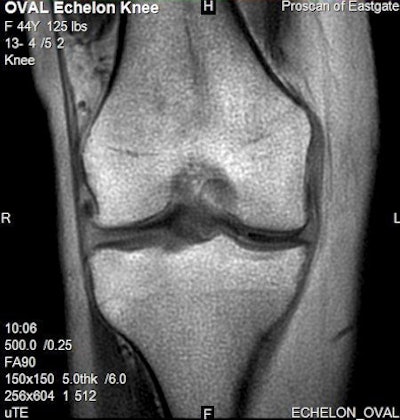

Meanwhile, Micro TE is an advanced musculoskeletal imaging protocol that offers better visualization of tendons and ligaments, and new applications in shoulder and spine imaging will be added. BeamSat TOF (time of flight) offers selective saturation of the circle of Willis.

![]() |

| Micro TE sequence (0.25-msec in this example) allows enhanced visualization of structures with very short T2 relaxation times (cartilage, tendons, ligaments) that cannot be seen with conventional imaging. |